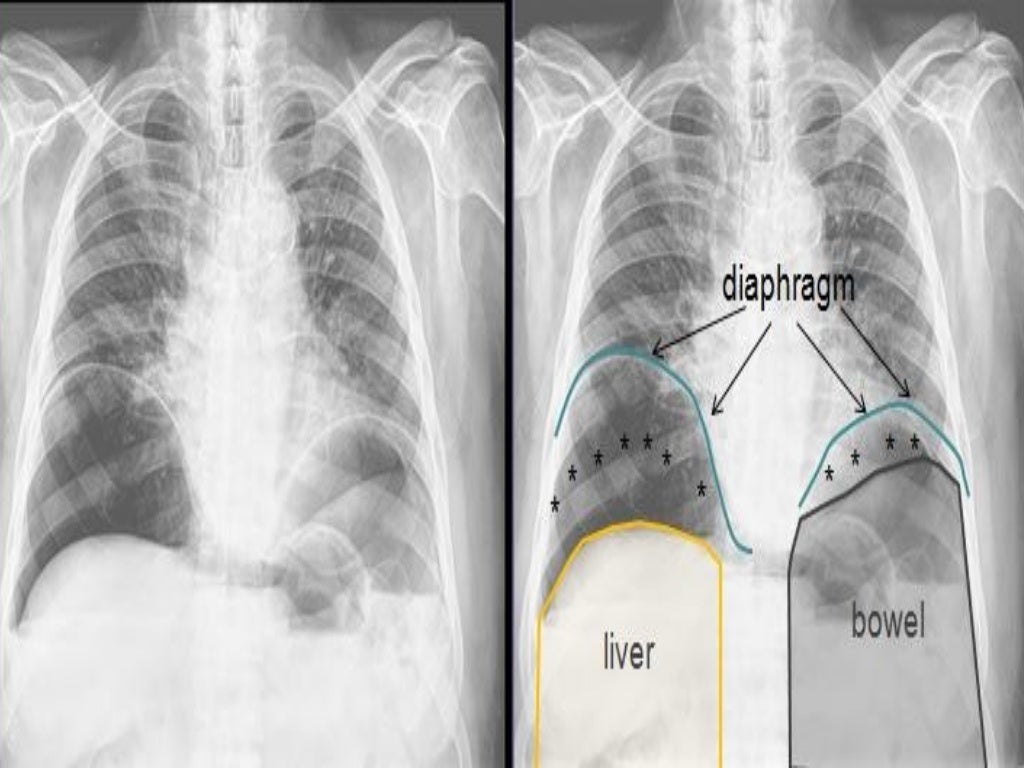

Abnormal gas pattern under diaphragm BMJ Case Reports Gas Near Diaphragm Web here's what causes these signs and symptoms — and how you can minimize them. This can be due to diaphragmatic irritation from surgeries Web hiatal hernia is when your stomach pushes itself up against an opening in your diaphragm into your chest,. Gas pain in the chest can result from. Web several nerves, soft tissues and blood vessels pass. Gas Near Diaphragm.

Free gas is seen below the diaphragm on plain chest roentgenogram taken Gas Near Diaphragm Web several nerves, soft tissues and blood vessels pass through the diaphragm. This can be due to diaphragmatic irritation from surgeries Web a diaphragm spasm is a sudden, involuntary contraction that can cause pain and. Web hiatal hernia is when your stomach pushes itself up against an opening in your diaphragm into your chest,. Web here's what causes these signs. Gas Near Diaphragm.

Gas under diaphragm Medicine Hack Gas Near Diaphragm Web here's what causes these signs and symptoms — and how you can minimize them. Web gas pain in the left shoulder blade is commonly a type of referred pain that arises from the abdomen or diaphragm, rather than actual gas near the shoulder. This can be due to diaphragmatic irritation from surgeries Web a diaphragm spasm is a sudden,. Gas Near Diaphragm.